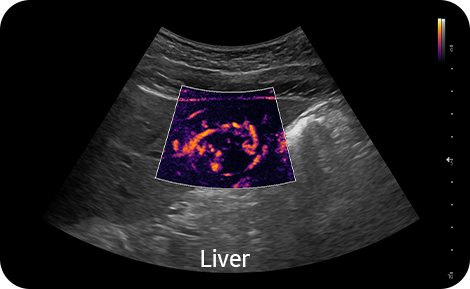

Vizualizace pomalého toku v mikrovaskulárních strukturách |

MV-Flow™ nabízí pokročilé barevné zobrazení pro vizualizaci pomalého průtoku v mikrovaskulárních strukturách. Vysoká snímková frekvence a pokročilé filtrování umožňují MV-Flow™ poskytnout detailní pohled na průtok krve, ve vztahu k okolní tkáni nebo patologii, se zvýšeným prostorovým rozlišením.

![]()